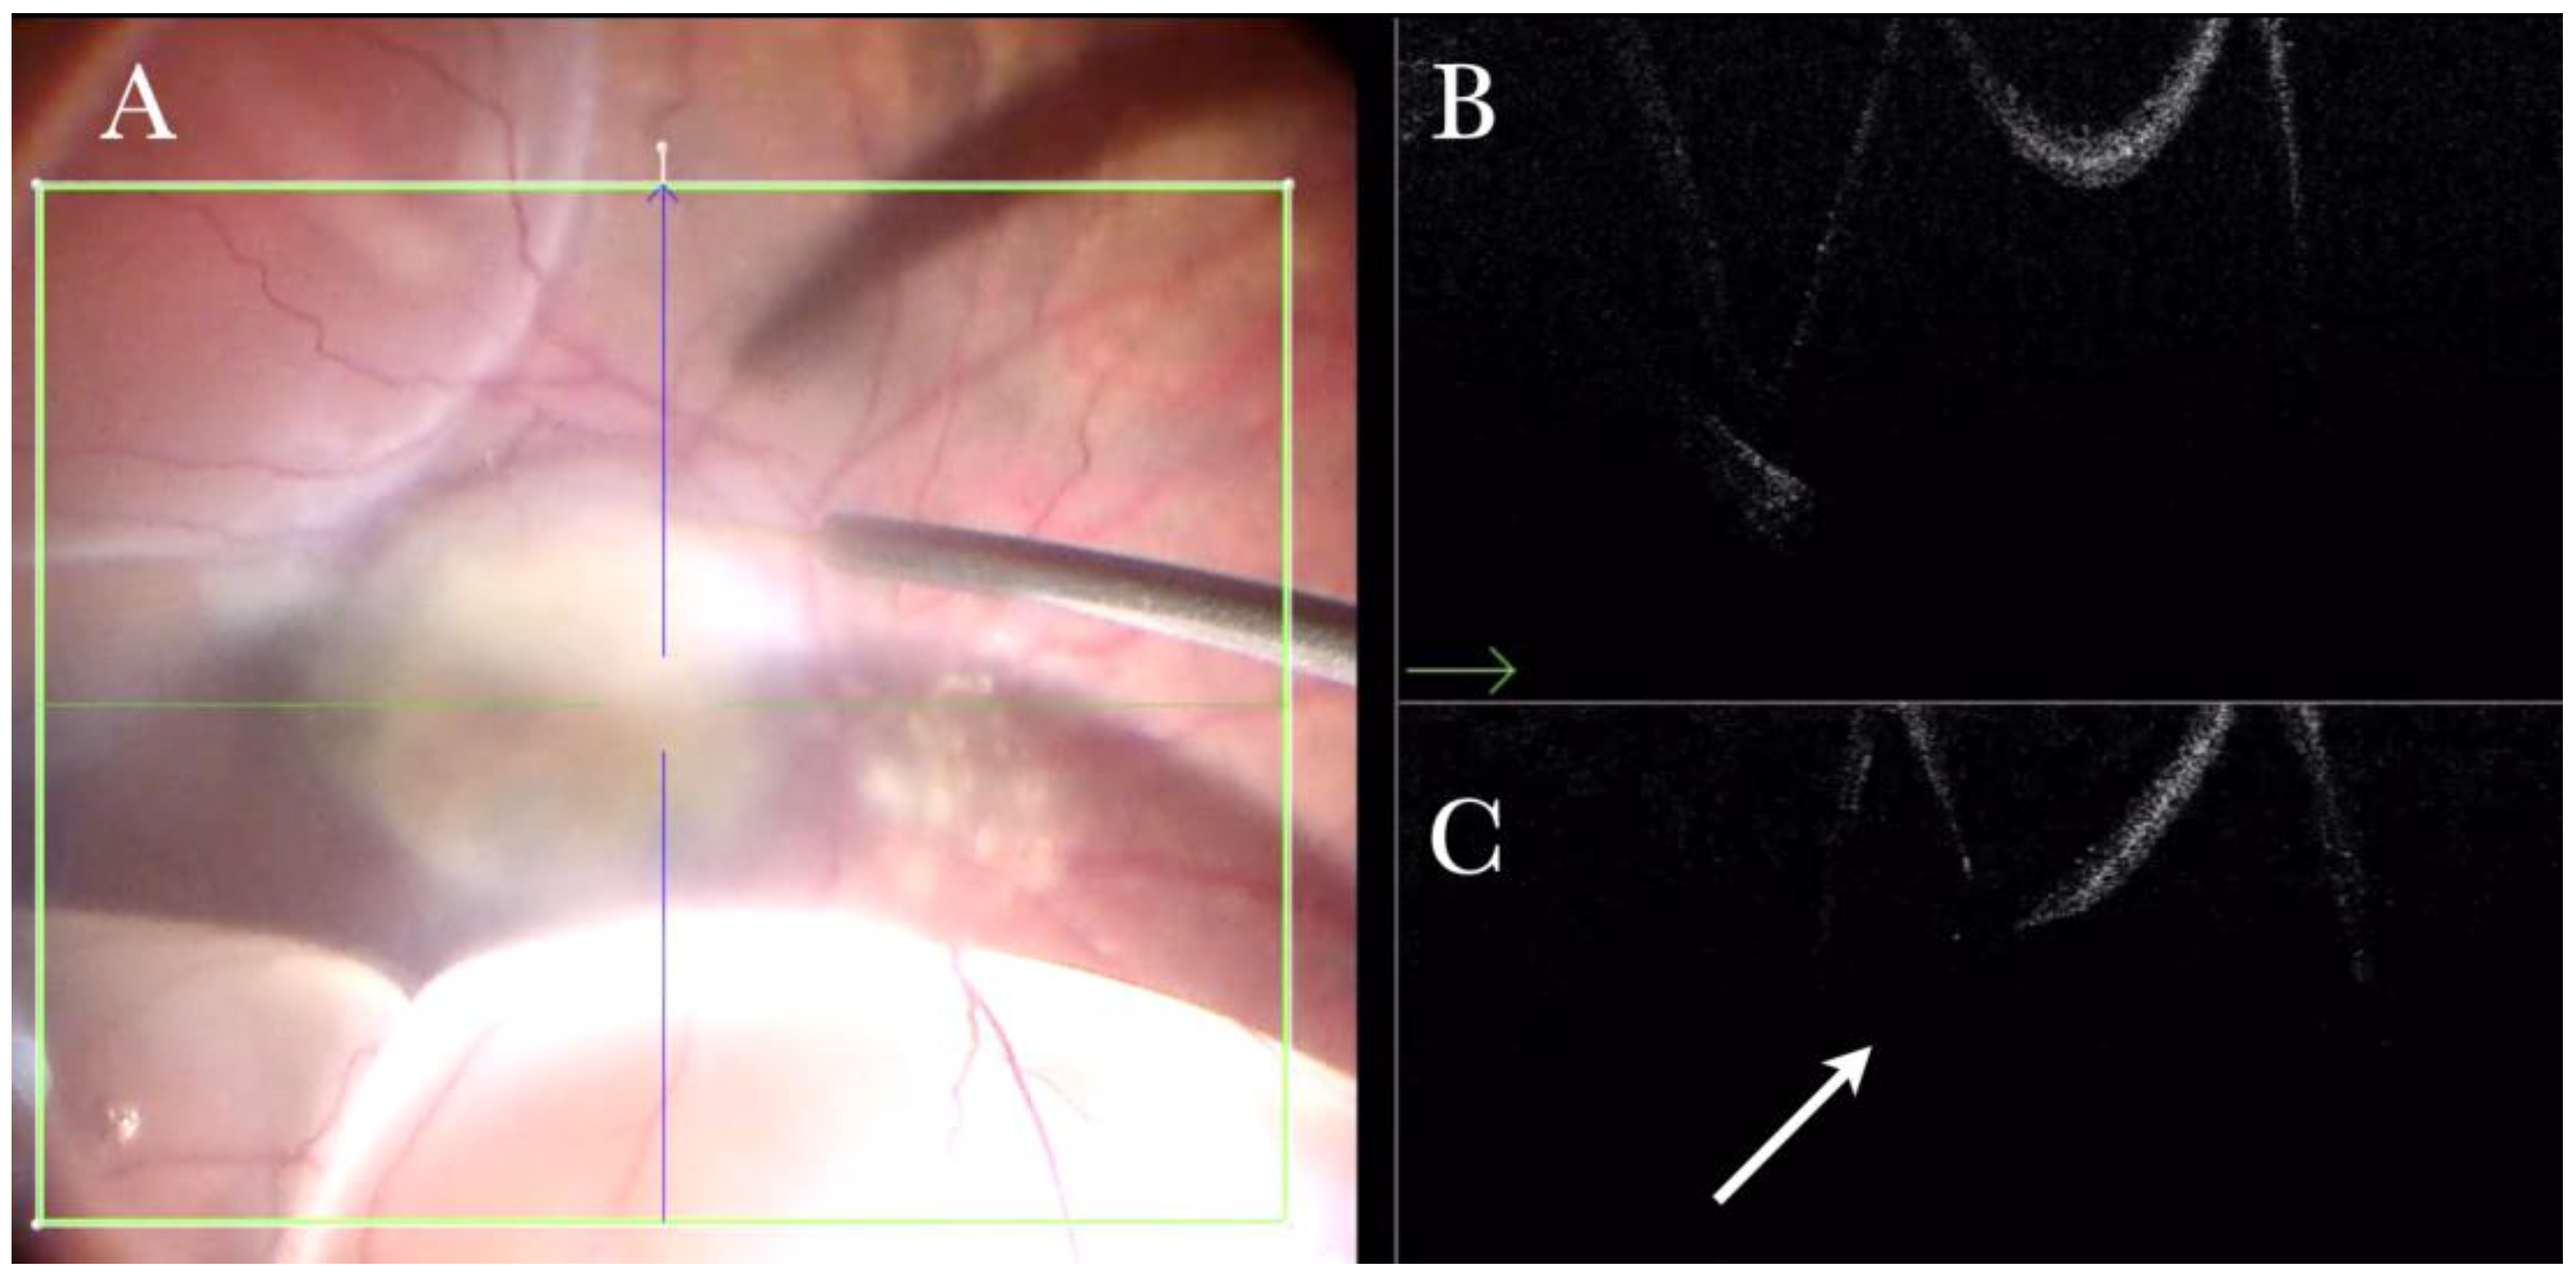

Figure 4.

(A) Microscope view of the macular area during peeling of an epiretinal membrane (ERM). The ERM is elevated. (The white box indicates the field-of-view of the OCT scan, the green circle within the white box represents the effective working distance and green and blue lines within the green circle show the vertical and horizontal scan planes). (B) Intraoperative optical coherence tomography (i-OCT) B horizontal (green arrow) scan during peeling. The ERM is elevated, and the macular profile is preserved where the ERM has been peeled. (C) i-OCT B vertical (blue arrow) scan during peeling. The ERM is elevated. The inner limiting membrane (ILM) is stretched and elevated where the ERM is peeled. The i-OCT allowed us to see the double simultaneous peeling of ERM and ILM.